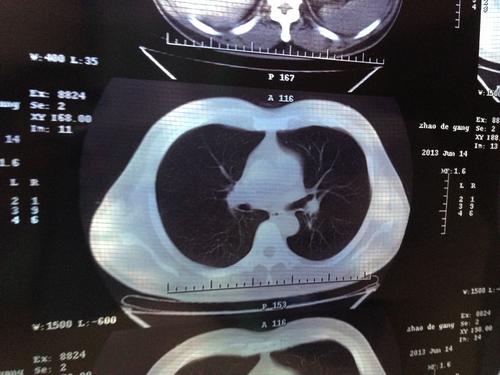

医学上的肺结节是指肺部直径不超过3厘米的圆形或准圆形疾病区域。直径不超过2厘米的称为小肺结节,直径小于1厘米的称为小肺结节。肺部小结节的特异性诊断和鉴别诊断是医学影像学中的一个临床难题。如何显示肺部小结节的具体内容是影像学的重要组成部分。对于没有具体临床表现和特征的大小肺结节,影像诊断非常重要,但对于具有明显特征的肺结节,即使是没有太多临床经验的医生也有同样明确的临床结论。随着螺旋CT成像技术的出现,肺部小结节的具体内容得到了更全面的显示,临床影响的准确诊断率得到了显著提高。与周围肺结节相比,其主要临床表现包括三个方面:

结节和肺的形态特征、水平面和周围部分的变化;血管变化贯穿上述三个方面。目前,肺结节的临床影像诊断最常用的是CT诊断和高千伏摄影。为了研究CT和高千伏摄影对肺结节临床检查的意义,选择了一种有效合理的肺结节临床检查方法。我院开展了一系列实验研究,报告如下。

螺旋CT对肺结节的诊断具有重要价值,对肺结节密度、钙化范围和支气管气象的诊断具有重要意义。螺旋CT诊断比x线诊断更准确(p < 0.05)。见表1。

实验结果表明,螺旋CT对肺结节的诊断具有重要价值,对肺结节密度、钙化范围和支气管气象的诊断具有重要意义。螺旋CT诊断比x线诊断更准确(p < 0.05)。因此,可以得出以下结论:利用螺旋CT诊断肺结节可以准确地为疾病的治疗提供重要的临床价值;在肺结节的临床影像学检查中,螺旋CT的检出率明显优于高千伏,具有较高的临床应用价值。